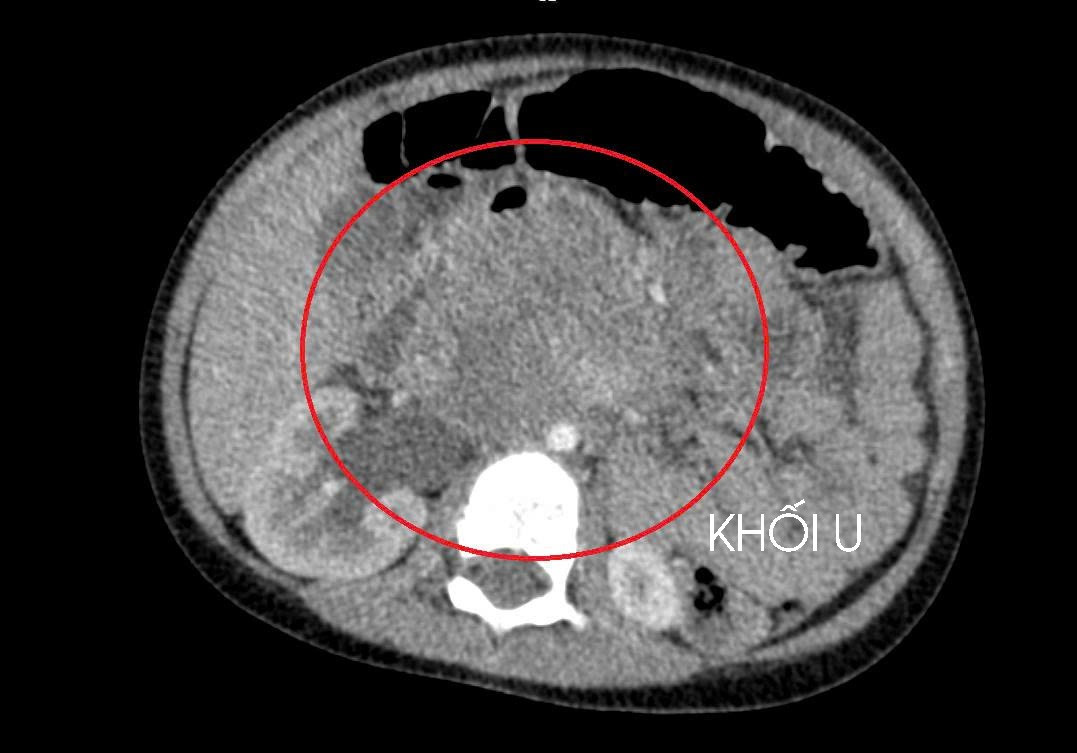

Qua thăm khám lâm sàng, chụp cắt lớp vi tính ổ bụng và siêu âm, các bác sĩ phát hiện một khối u lớn sau phúc mạc, chèn ép thận. Sau quá trình đánh giá toàn diện, kết quả cho thấy bé mắc ung thư tinh hoàn, theo dõi di căn gan và phổi.

ut-tinh-hoan-2.jpg

Khối u ung thư do tinh hoàn ẩn - Ảnh BVCC